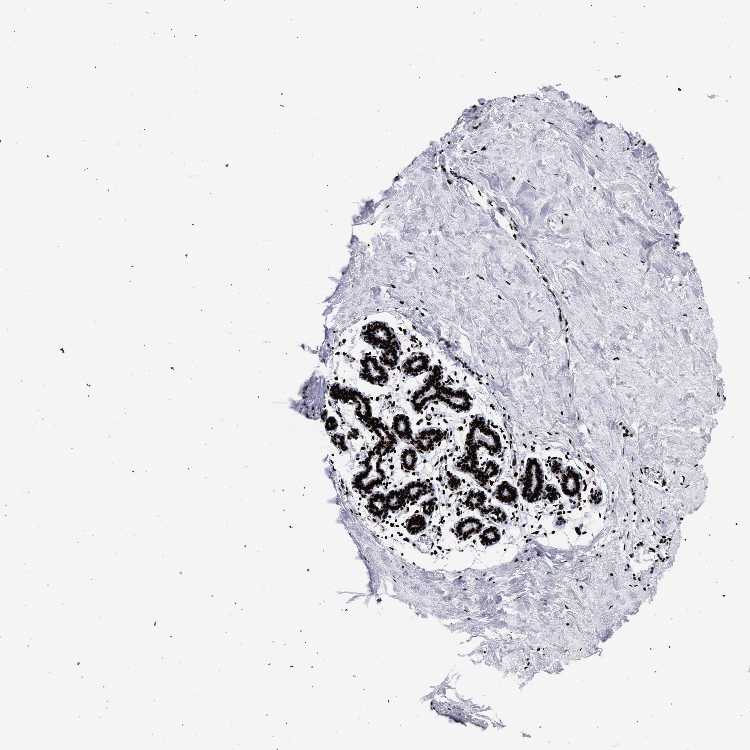

BREAST - Antibody stainingi

Antibody staining in the annotated cell types in the current human tissue is reported as not detected, low, medium, or high, based on conventional immunohistochemistry profiling in selected tissues. This score is based on the combination of the staining intensity and fraction of stained cells.

Each image is clickable and will lead to virtual microscopy that enables deeper exploration of all samples and also displays staining intensity scores, fraction scores and subcellular localization as well as patient and tissue information for each sample.

Antibody HPA001609Antibody HPA001666Antibody CAB010894

Adipocytes Medium--

Glandular cells HighHighHigh

Myoepithelial cells HighHighHigh